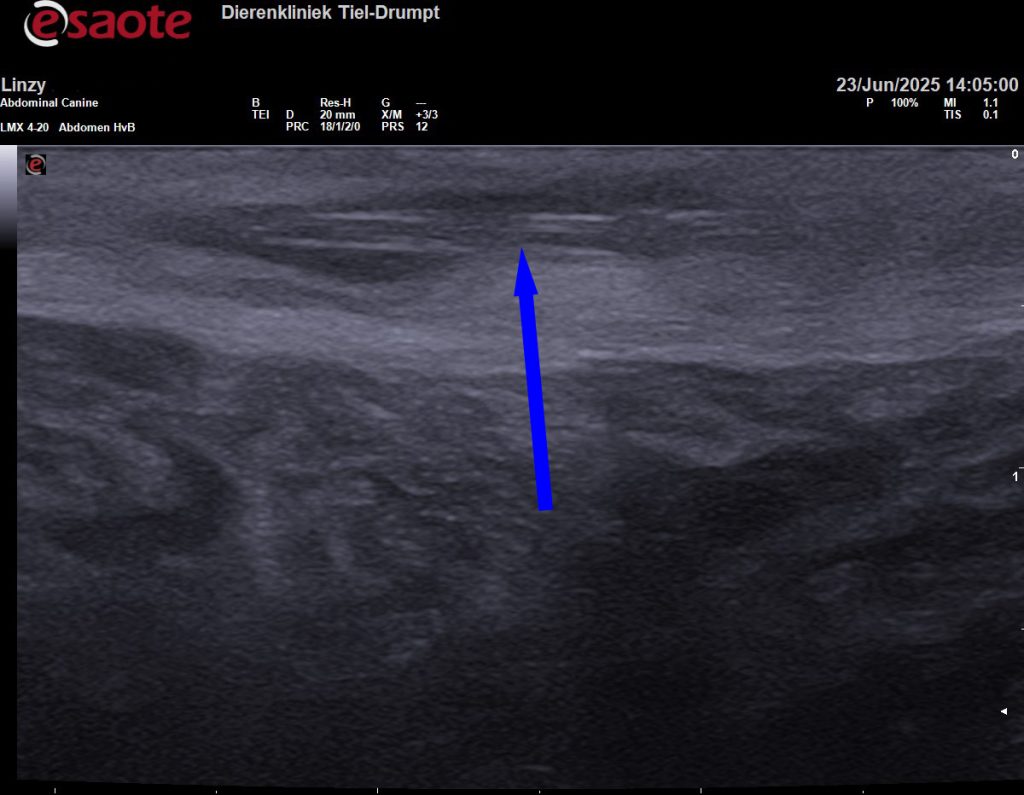

Grasaren kunnen ook op andere plaatsen voorkomen, zoals tussen de tenen of op willekeurige plekken onder de huid. Onderstaande echobeeld is van een grasaar die op een dijbeen van een hond onder de huid was “gekropen”.